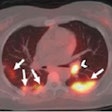

Dosimetry key in Lu-177 cancer therapy